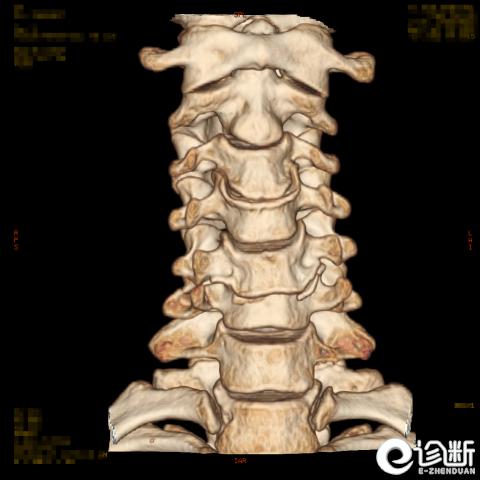

颈椎骨折

CT:显示椎管(骨折碎片可压迫椎管)

分型:

根据骨折的水平及位置:C1-Jeferson骨折:前后弓骨折

C1-侧块骨折

C2-Hangman骨折(峡部):Levine分型

C2齿突骨折1型、2型、3型

C3-7骨折:

棘突骨折(Clay shoveler骨折):C6,7,T1(C7最常见)